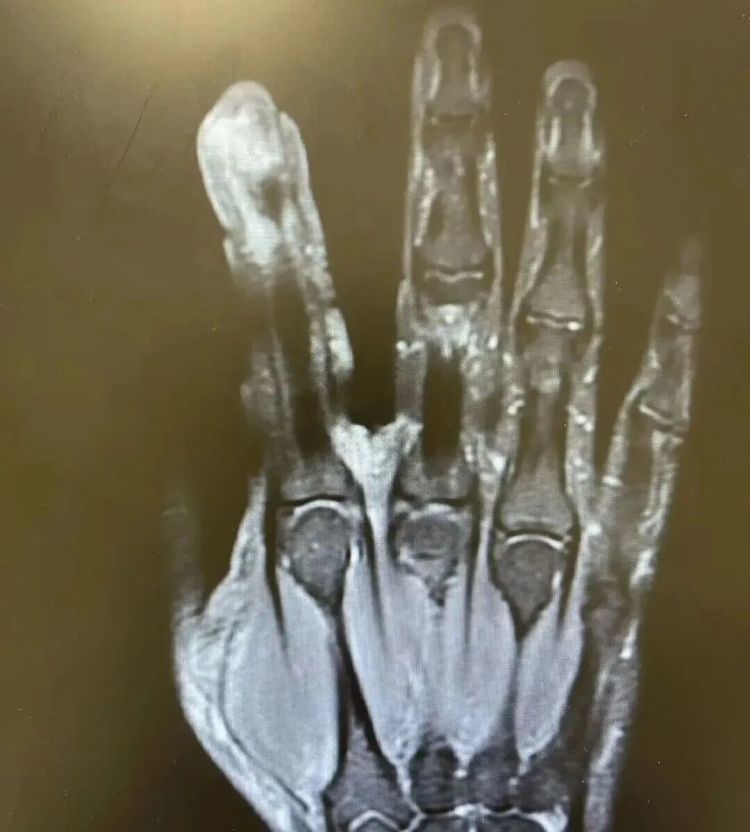

贯串涂了三天,伤口不仅不见好,反倒红肿、溃烂得愈加严重。当他赶到病院时,左手食指仍是肿得像萝卜,指尖处发白溃烂,疼得连水杯都抓不住。

经搜检,李年老破溃的左手指尖严重感染,厌氧消化链球菌顺着龙套处钻到骨头里,激发了严重骨髓炎。医师进击手术,帮李年老“刮掉”坏死的骨头碎屑,断根了坏死的肌肉与皮肤。

医师默示。如若再晚一步,不仅手指保不住,还可能会引起脓毒血症,以致危及人命。